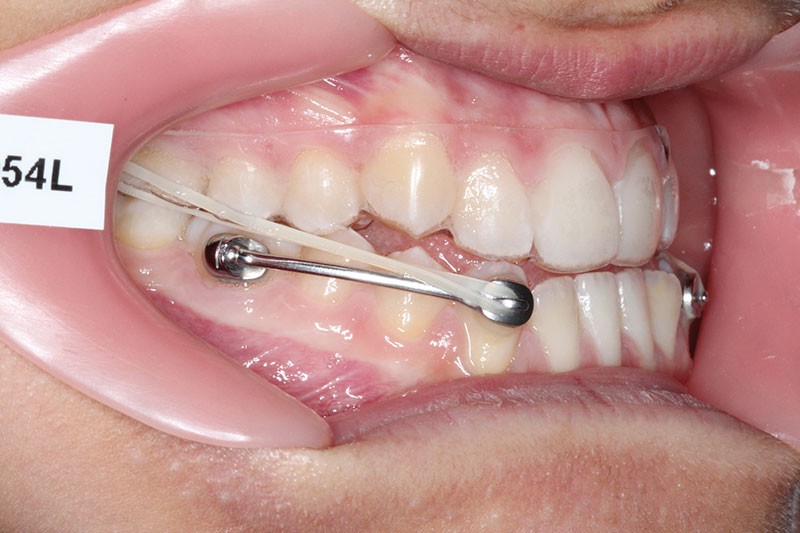

1re phase : recul des secteurs latéraux mandibulaires avec le Motion Classe III Carriere (fig. 4 à 6)

Nous mettons en place des bras latéraux Motion associés à des élastiques intermaxillaires ancrés sur des brackets sur 17 et 27 et une gouttière thermoformée maxillaire portée jour et nuit :

L’objectif de cette étape est d’obtenir un recul des secteurs latéraux mandibulaires afin de positionner les molaires et canines en classe I et de réorienter le plan d’occlusion en haut en avant.